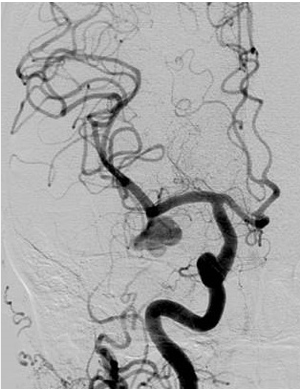

脳動静脈奇形(AVM)

脳の動脈が毛細血管を介さずに「ナイダス」と呼ばれる血管のかたまりで直接静脈につながっており、動脈血が直接静脈に流入している病気です。脳出血、くも膜下出血、けいれん発作の原因となることがあります。治療には開頭摘出術、脳血管内手術(塞栓術)、放射線治療があり、これらを組み合わせた集学的治療が必要な場合も多くあります。

術前の造影写真です。〇内に脳動静脈奇形が描出されています。

塞栓術および摘出術後の造影写真です。脳動静脈奇形は消失しております。